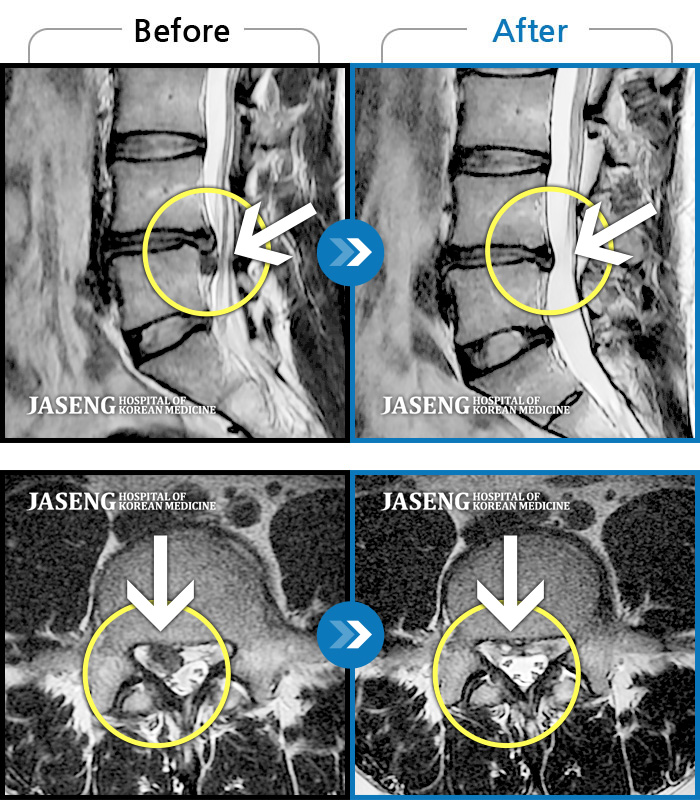

MRI 치료사례

우측 허리 골반이 아프고, 우측 다리가 저리고 당기며 힘이 빠진다.